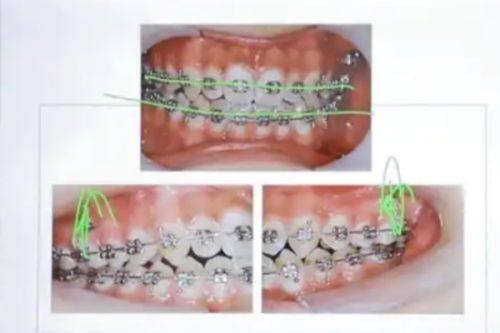

牙齿美容整形多少钱?2026年最新价格揭秘与注意事项! 本文围绕2026年牙齿美容整形价格及注意事项展开。牙齿整形费用参考范围8000 - 30000元,受畸形程度、地区、矫治器材料等因素影响。不同矫治器材料费用有别,国产亲民、进口稍贵、隐形更贵。还介绍了医院医生、治疗方案等影响价格的其他因素。同时给出选择正规机构、与医生沟通等注意事项,助大家选合适方案美牙。 牙齿美白 2026年03月04日 0 点赞 0 评论 7 浏览